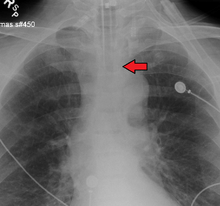

An endotracheal tube in good position on CXR. Arrow marks the tip.

An endotracheal tube not deep enough. Arrow marks the tip.

No single method for confirming tracheal tube placement has been shown to be 100% reliable. Accordingly, the use of multiple methods for confirmation of correct tube placement is now widely considered to be the standard of care.[32] Such methods include direct visualization as the tip of the tube passes through the glottis, or indirect visualization of the tracheal tube within the trachea using a device such as a bronchoscope. With a properly positioned tracheal tube, equal bilateral breath sounds will be heard upon listening to the chest with a stethoscope, and no sound upon listening to the area over the stomach. Equal bilateral rise and fall of the chest wall will be evident with ventilatory excursions. A small amount of water vapor will also be evident within the lumen of the tube with each exhalation and there will be no gastric contents in the tracheal tube at any time.[31]

Ideally, at least one of the methods utilized for confirming tracheal tube placement will be a measuring instrument. Waveform capnography has emerged as the gold standard for the confirmation of tube placement within the trachea. Other methods relying on instruments include the use of a colorimetric end-tidal carbon dioxide detector, a self-inflating esophageal bulb, or an esophageal detection device.[33] The distal tip of a properly positioned tracheal tube will be located in the mid-trachea, roughly 2 cm (1 in) above the bifurcation of the carina; this can be confirmed by chest x-ray. If it is inserted too far into the trachea (beyond the carina), the tip of the tracheal tube is likely to be within the right main bronchus — a situation often referred to as a "right mainstem intubation". In this situation, the left lung may be unable to participate in ventilation, which can lead to decreased oxygen content due to ventilation/perfusion mismatch.[34]